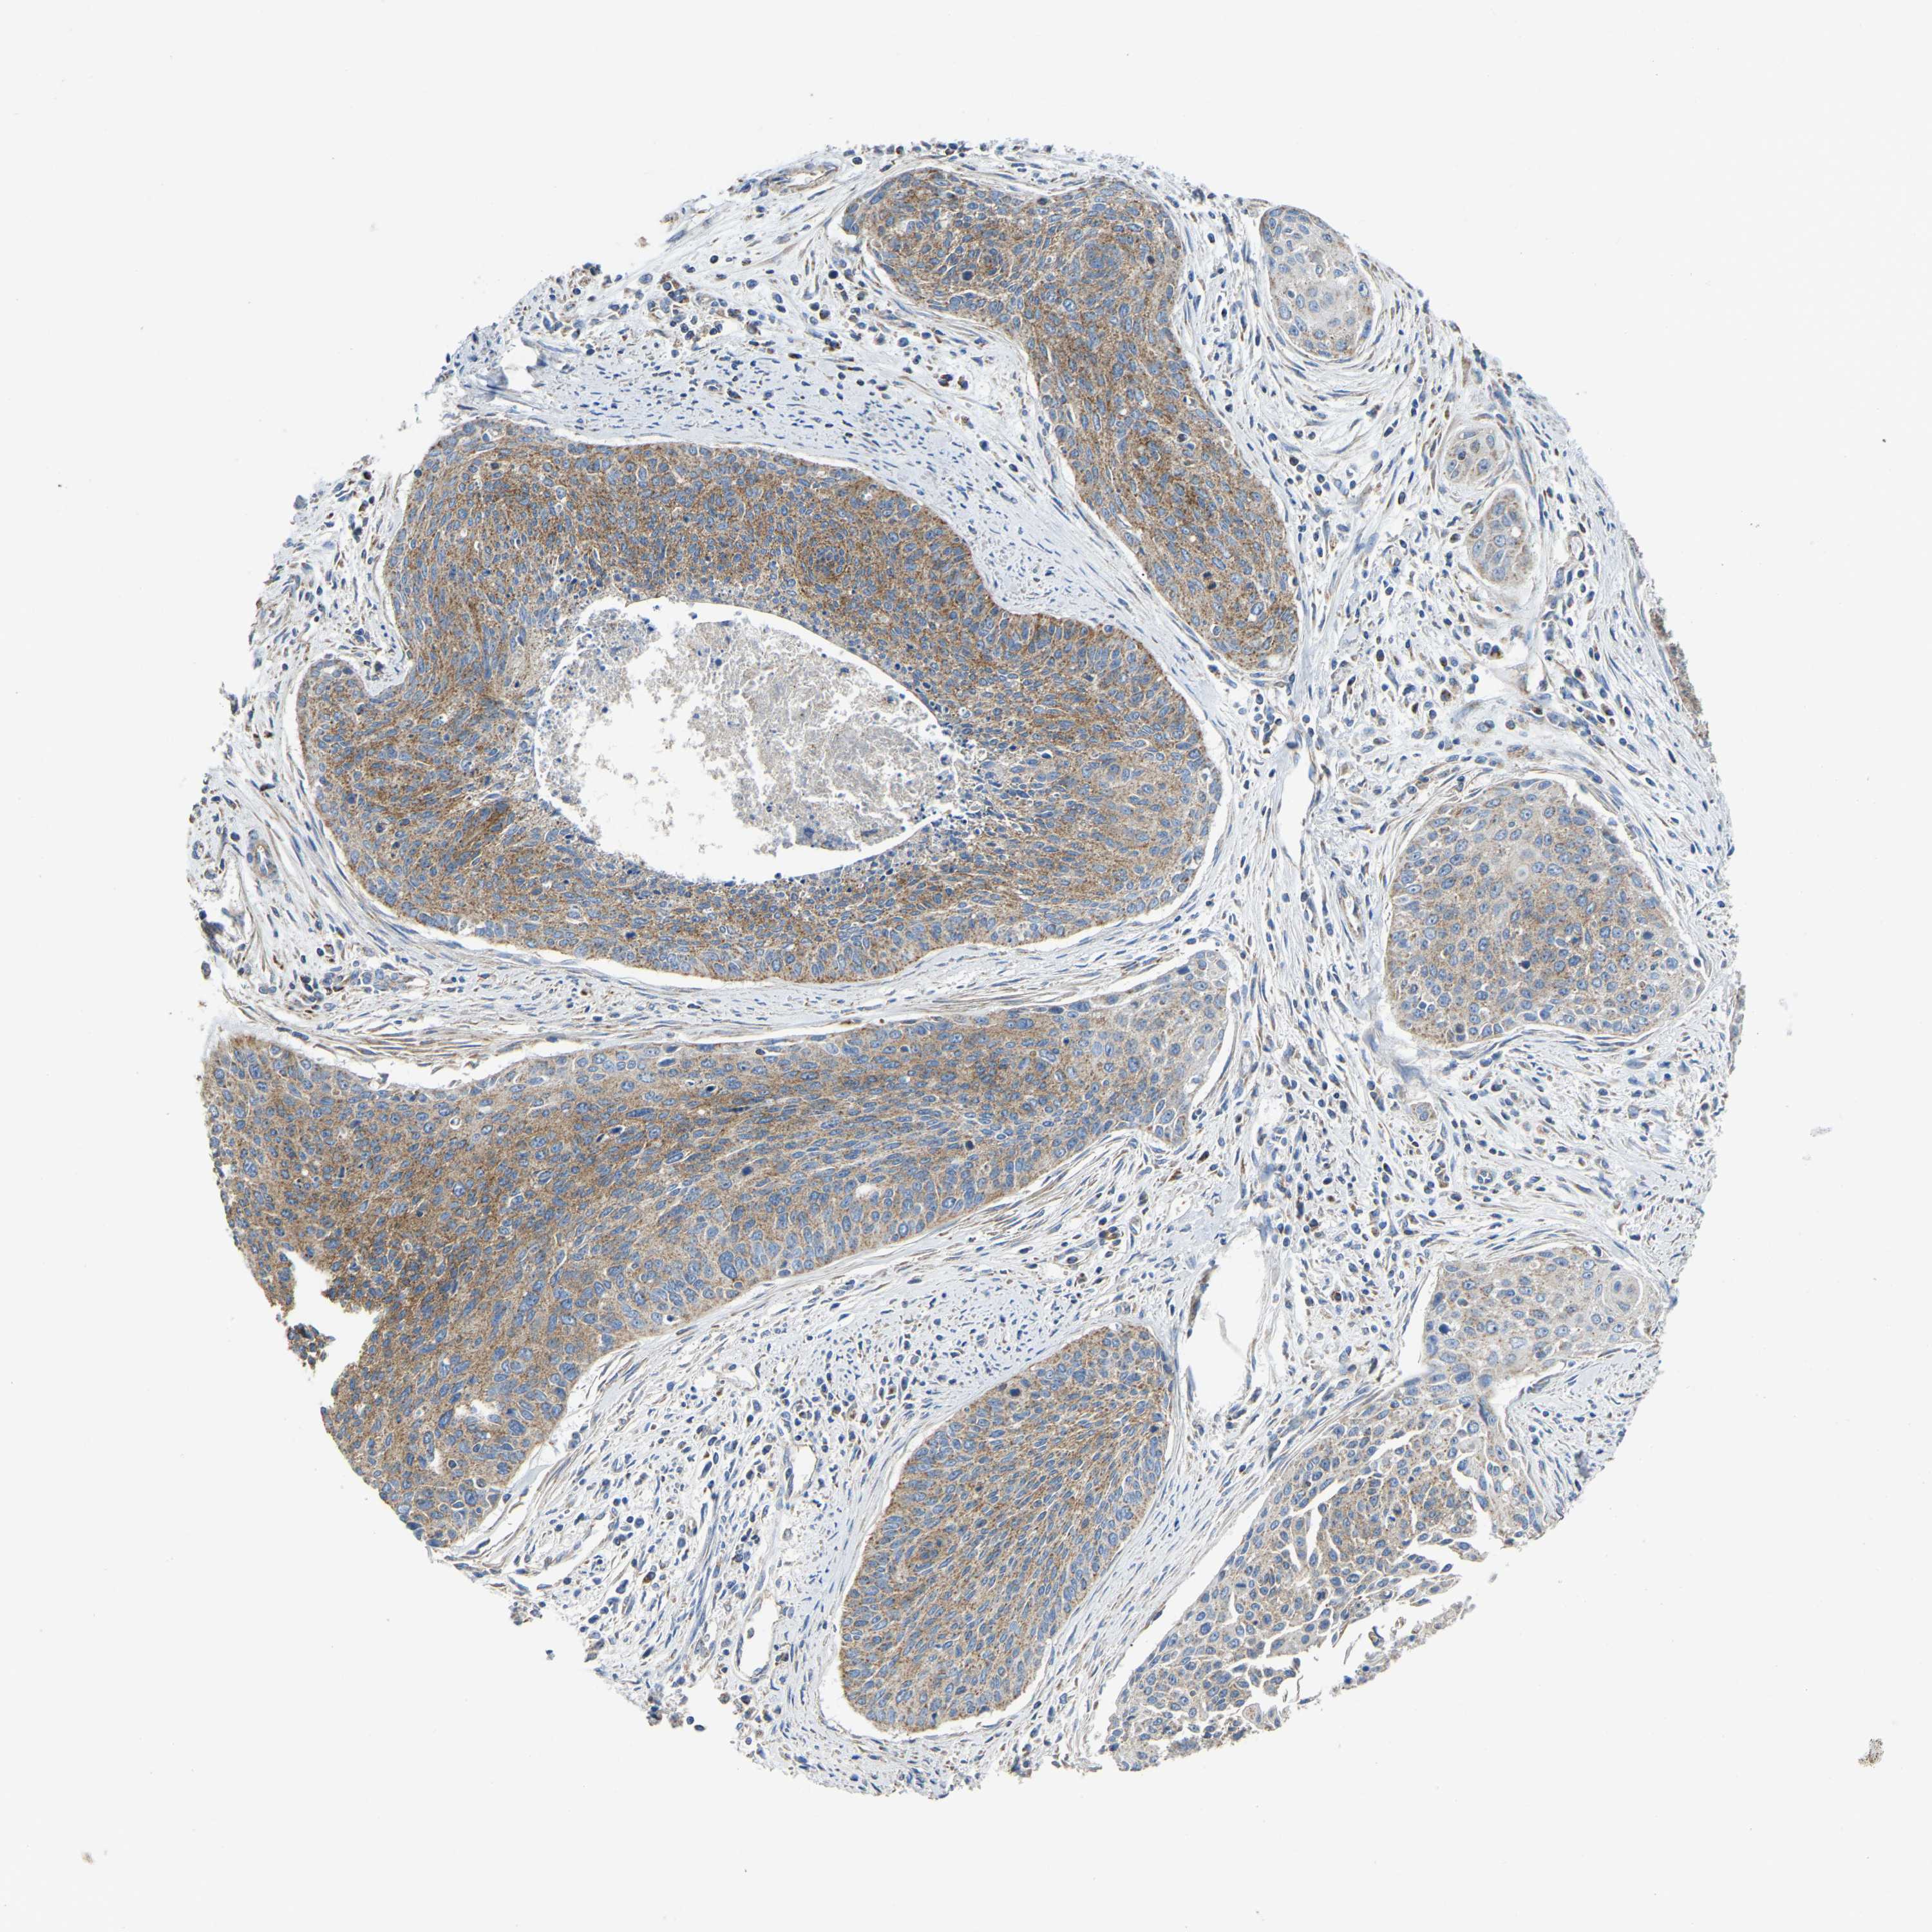

CERVICAL CANCER - Protein expressioni

A mouse-over function shows sample information and annotation data. Click on an image to view it in a full screen mode. Samples can be filtered based on level of antibody staining by selecting one or several of the following categories: high, medium, low and not detected. The assay and annotation is described here.

Note that samples used for immunohistochemistry by the Human Protein Atlas do not correspond to samples in the TCGA dataset.

Antibody stainingi

Antibody staining in the annotated cell types in the current human tissue is reported as not detected, low, medium, or high, based on conventional immunohistochemistry profiling in selected tissues. This score is based on the combination of the staining intensity and fraction of stained cells.

Each image is clickable and will lead to virtual microscopy that enables deeper exploration of all samples and also displays staining intensity scores, fraction scores and subcellular localization as well as patient and tissue information for each sample.

Antibody HPA018990

Antibody HPA018993

Antibody HPA018996

Antibody HPA024089

Adenocarcinoma, NOS